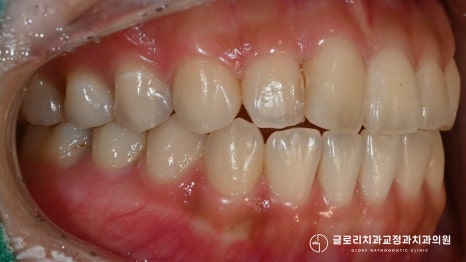

교합도 정상 범주에 속해 올바르게 맞물리고 있었죠.

어금니 교합도 1치대 2치대로 잘 맞고 있네요.